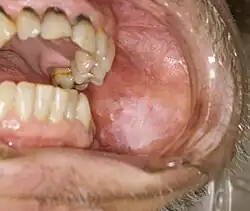

Als Leukoplakie (von altgriechisch λευκός leukós, deutsch ‚weiß‘ und πλάξ, Genitiv πλακός plakós, deutsch ‚Platte, Fläche‘ – wörtlich „weiße Fläche“) gelten alle weißen, nicht abwischbaren Effloreszenzen der Schleimhaut. Die Leukoplakie ist eine Keratinisierungsstörung mit zellulären und epithelialen Atypien. Als Ursachen werden Nikotin- und Alkoholmissbrauch sowie mechanische Reize genannt. Die Leukoplakie gehört allgemein zu den fakultativen Präkanzerosen – wobei erosive und verruköse Leukoplakien ein Entartungspotential zum Plattenepithelkarzinom zeigen. Flache Leukoplakien sind im Allgemeinen harmlos, verruköse (warzenartige) Leukoplakien sind histologisch echte Carcinomata in situ.[1] Differentialdiagnostisch müssen obligat folgende Pathologien miteinbezogen werden: Friktionskeratose, Morsicatio buccarum, Candidiasis, Haarleukoplakie, weißer Schwammnävus, Lichen ruber planus, Chronisch Diskoider Lupus erythematodes (CDLE) und Verätzungen.

- Leukoplakia simplex (plana): homogener, weißer, im Allgemeinen scharf begrenzter Schleimhautbezirk mit glatter Oberfläche. In der Regel harmlos, Entartungsraten werden bis drei Prozent angegeben.[2]

- Leukoplakia verrucosa: Oberfläche ist warzig aufgeworfen. Karzinomrisiko: 11 Prozent (je nach Untersuchung bis zu 20 Prozent)

- Leukoplakia erosiva: Unregelmäßige Leukoplakie mit roten Arealen. Entartungsrate etwa (30 bis) 38 Prozent[2]